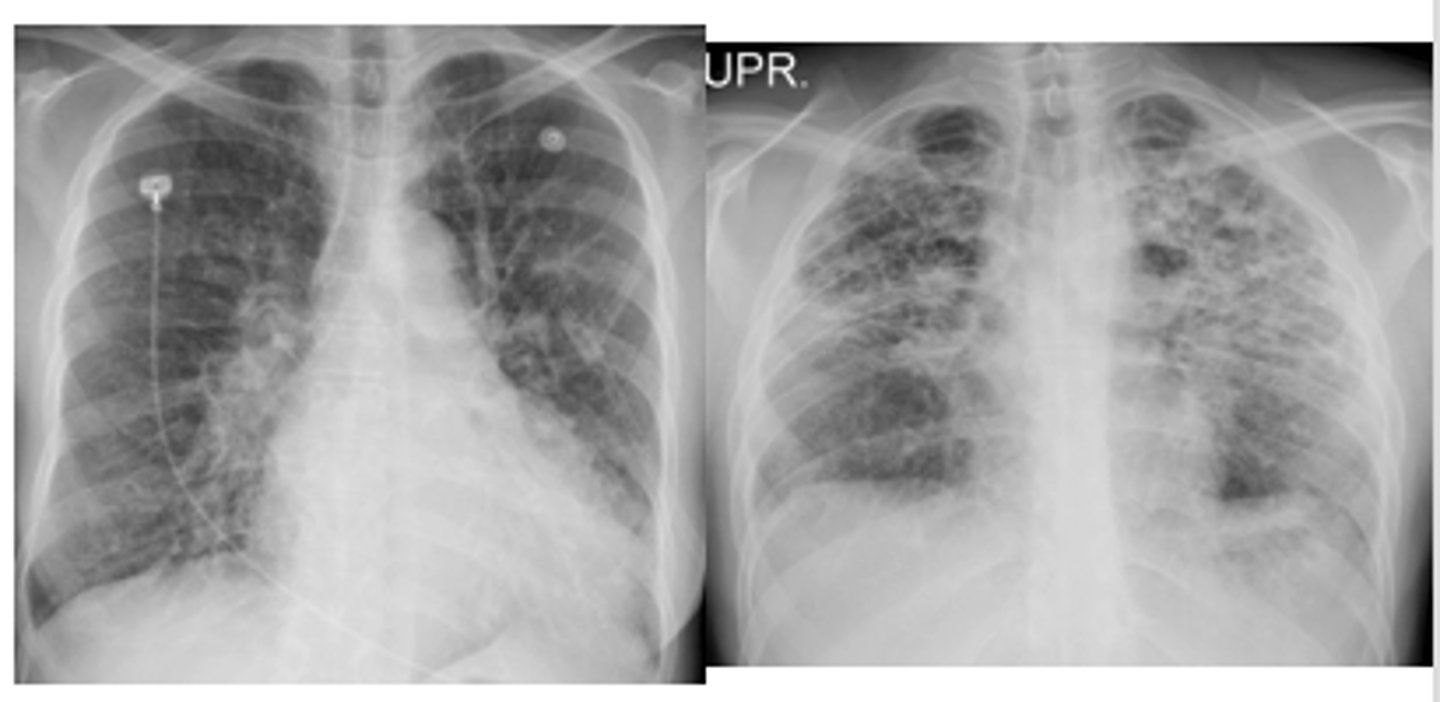

What is ARDS and what is the etiology?

oCapillaries are "leaky" and fluid shifts into the lungs from the blood supply through the capillaries - alveolar infiltrates.

oInitial insult to the alveoli usually caused by either alveolar or vascular damage.

oIncreases the permeability of the capillaries surrounding the alveoli and causes protein-rich fluid to fill the alveolar sacs.

ARDS x-ray appearance

"white out appearance" sometimes with sparing of costophrenic angles

<p>"white out appearance" sometimes with sparing of costophrenic angles</p>